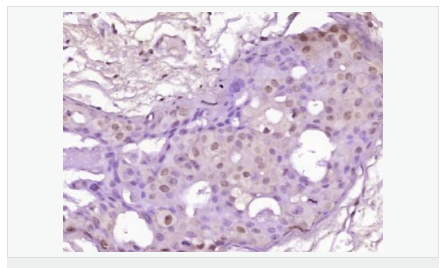

| 產品應用 | WB=1:500-2000 ELISA=1:5000-10000 IHC-P=1:100-500 IHC-F=1:100-500 Flow-Cyt=0.2μg /test IF=1:100-500 (石蠟切片需做抗原修復) not yet tested in other applications. optimal dilutions/concentrations should be determined by the end user. |

| 細胞定位 | 細胞核 細胞漿 細胞膜 |